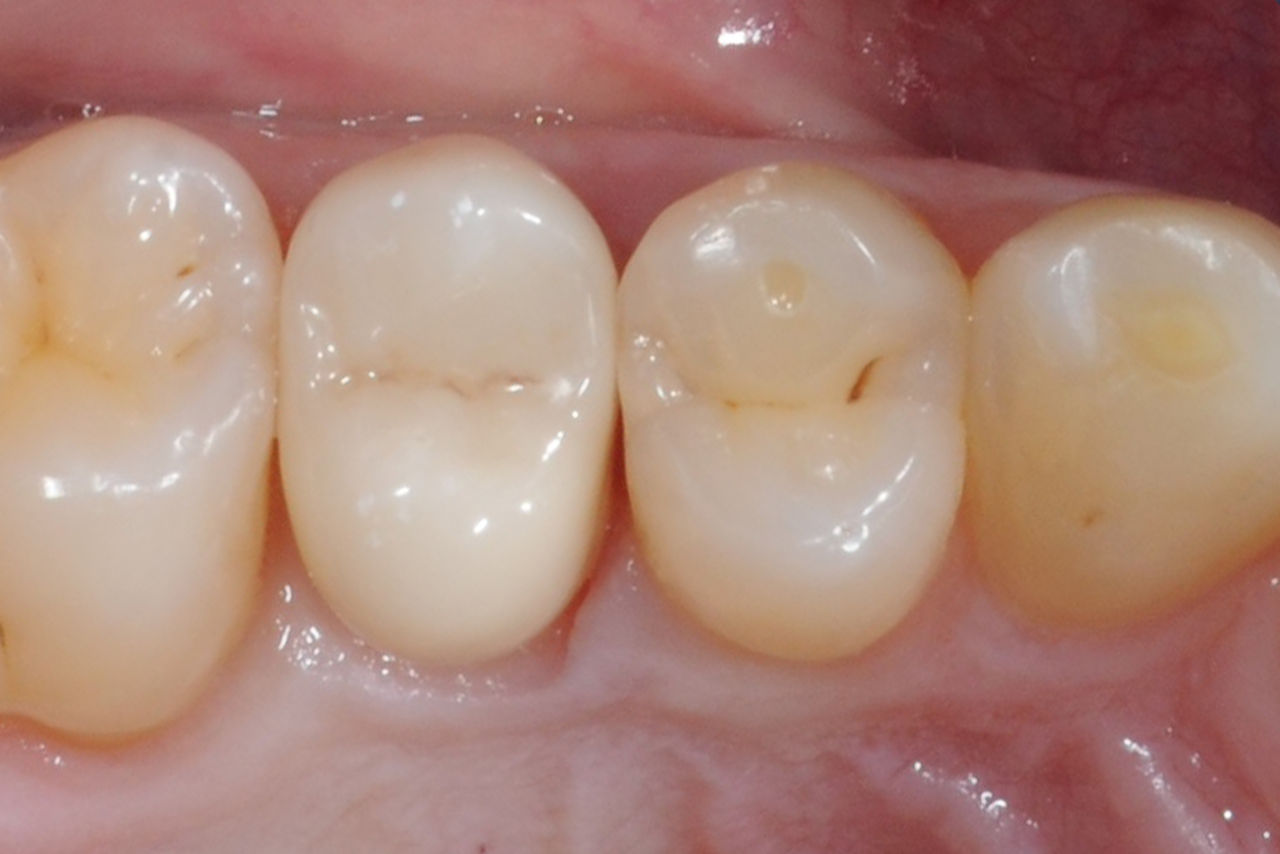

Before: Tooth 26 presenting decay and a failing direct composite restoration.

After: Highly aesthetic and functional lithium disilicate ceramic crown.